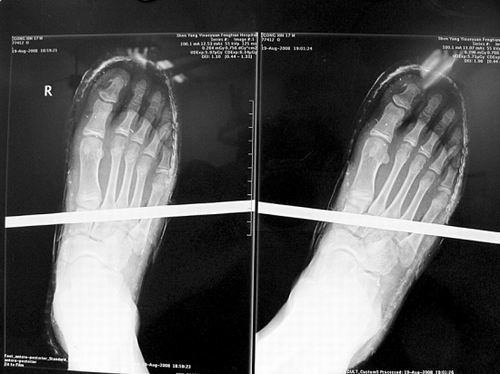

X光片顯示無大礙

事發時男孩穿著一雙布鞋,骨外二科陳賓醫生操起剪刀,將布鞋一塊塊剪掉。經X光透視,醫生驚奇地發現:男孩雖然被鋼筋穿透了右腳,但骨頭、大的血管和神經都沒受任何傷害!

20日,記者從X光片子上看到,鋼筋避開了男孩腳掌骨頭密集的部位,而是從腳弓處穿過,這個部位基本上以軟組織為主!罢鏇]想到,太神奇了!”幾名醫生連聲感嘆,術中,他們分工合作,小心翼翼地將鋼筋取出,并做了引流、清創、包扎。